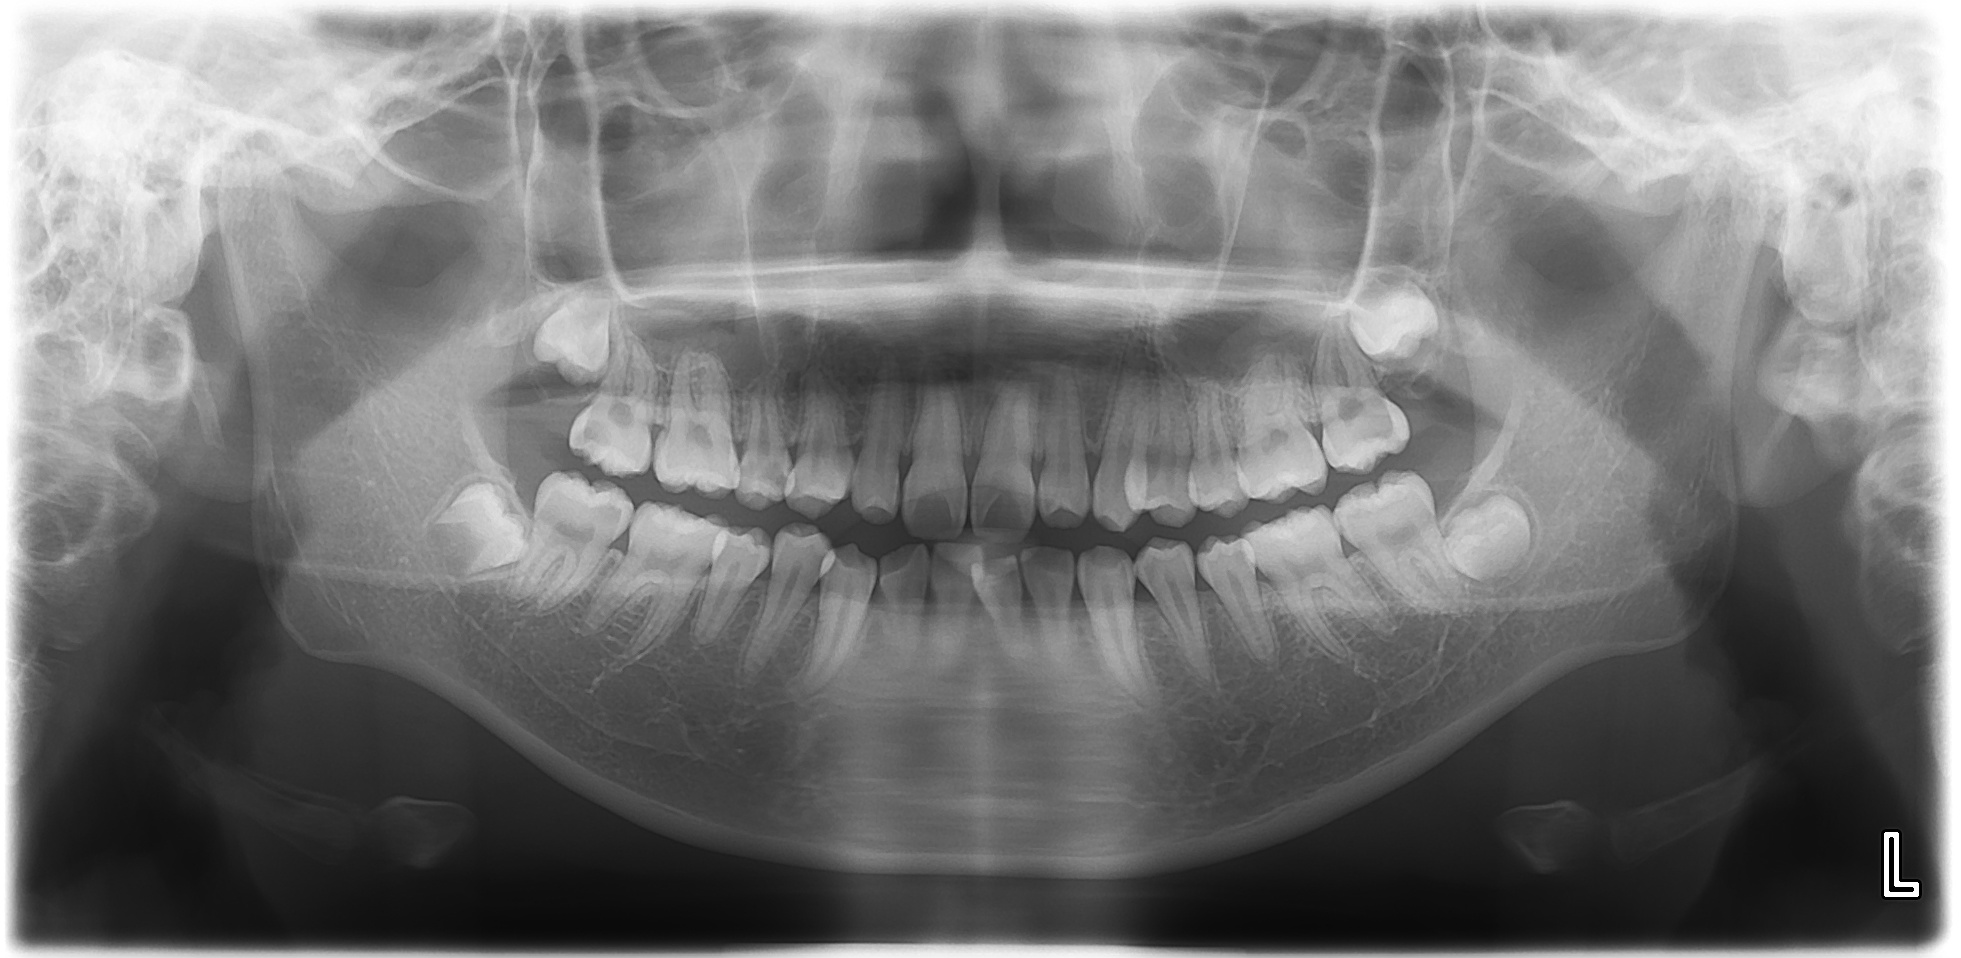

オリエント歯科では、まずはスタートとして、ご自身のお口の中がどういう状態なのかということをお伝えしているようにしています。そのため、受診された方のお口の中の写真を撮らせていただいています。正面から、右側から、左側から、上顎全体、下顎全体、右上、右下、左上、左下と9枚記録させていただくことが多いです。また必要に応じてレントゲン写真を撮らせていただきます。

カウンセリングをするときのパソコン画面イメージです。